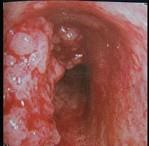

问题 47岁男性,咳嗽、胸痛、痰中带血、消瘦4个月,支气管镜、CT如图,可能的诊断是 ( )

选项 A.肺结核 B.肉芽肿 C.支气管脂肪瘤 D.错构瘤 E.气管癌

答案 E